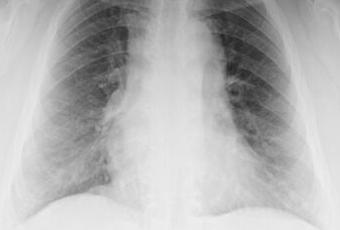

LA PROYECCION RADIOLOGICA OBTENIDA NOS MUESTRA LOS SIGUIENTES HALLAZGOS:

-Tejidos blandos, con densidad conservada, simétricos, sin evidencia de alteraciones.

-Estructuras óseas, sin evidencia de lesiones líticas, blásticas o perdida de la contigüidad.

-Vía aérea permeable.

-Mediastino, sin alteraciones. Existe calcificación en topografía de botón aórtico.

-Corazón, con índice cardiotorácico menor a 0.5.

-Hilios pulmonares, con adecuada densidad.

-Trama bronco-vascular, conservada.

-Campos pulmonares, con aumento de la densidad hacia áreas basales, dando un aspecto sutil en vidrio esmerilado.

-Recesos cardiofrénicos y costofrénico sin alteraciones.

OPINIÓN RADIOLÓGICA:

EN EL PRESENTE ESTUDIO RADIOGRÁFICO, CON IMÁGENES SUGERENTES DE PROCESO NEUMÓNICO A NIVEL BASAL BILATERAL.

ATEROESCLEROSIS BOTÓN AÓRTICO.

CORRELACIONAR CON DATOS E HISTORIA CLINICA DEL PACIENTE